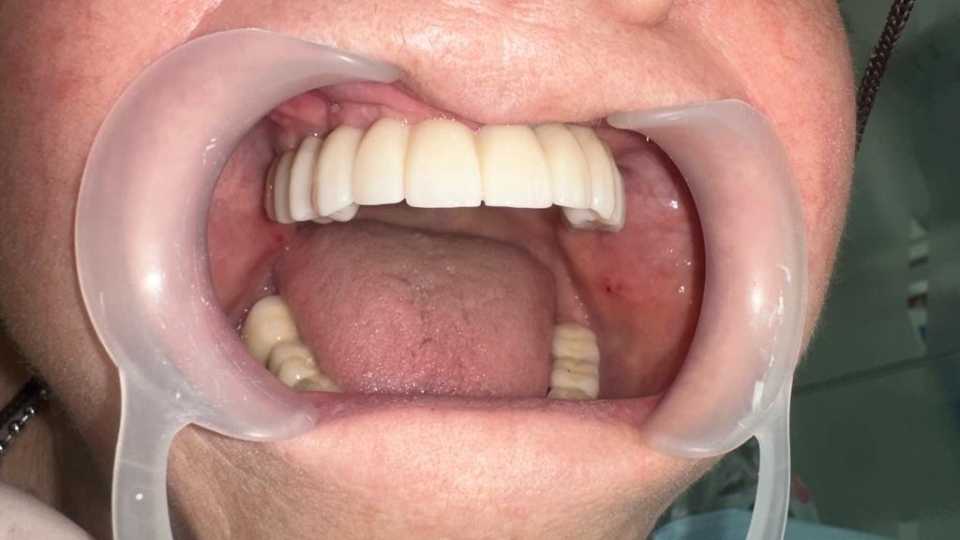

Sub anestezie generală s-au inserat 4 implanturi zigomatice și 2 implanturi pterigoide și 1 implant dentar normal cu ajutorul cărora am realizat o lucrare dentară protetică fixă din ceramica pe zirconiu insurubabila de 14 elemente.